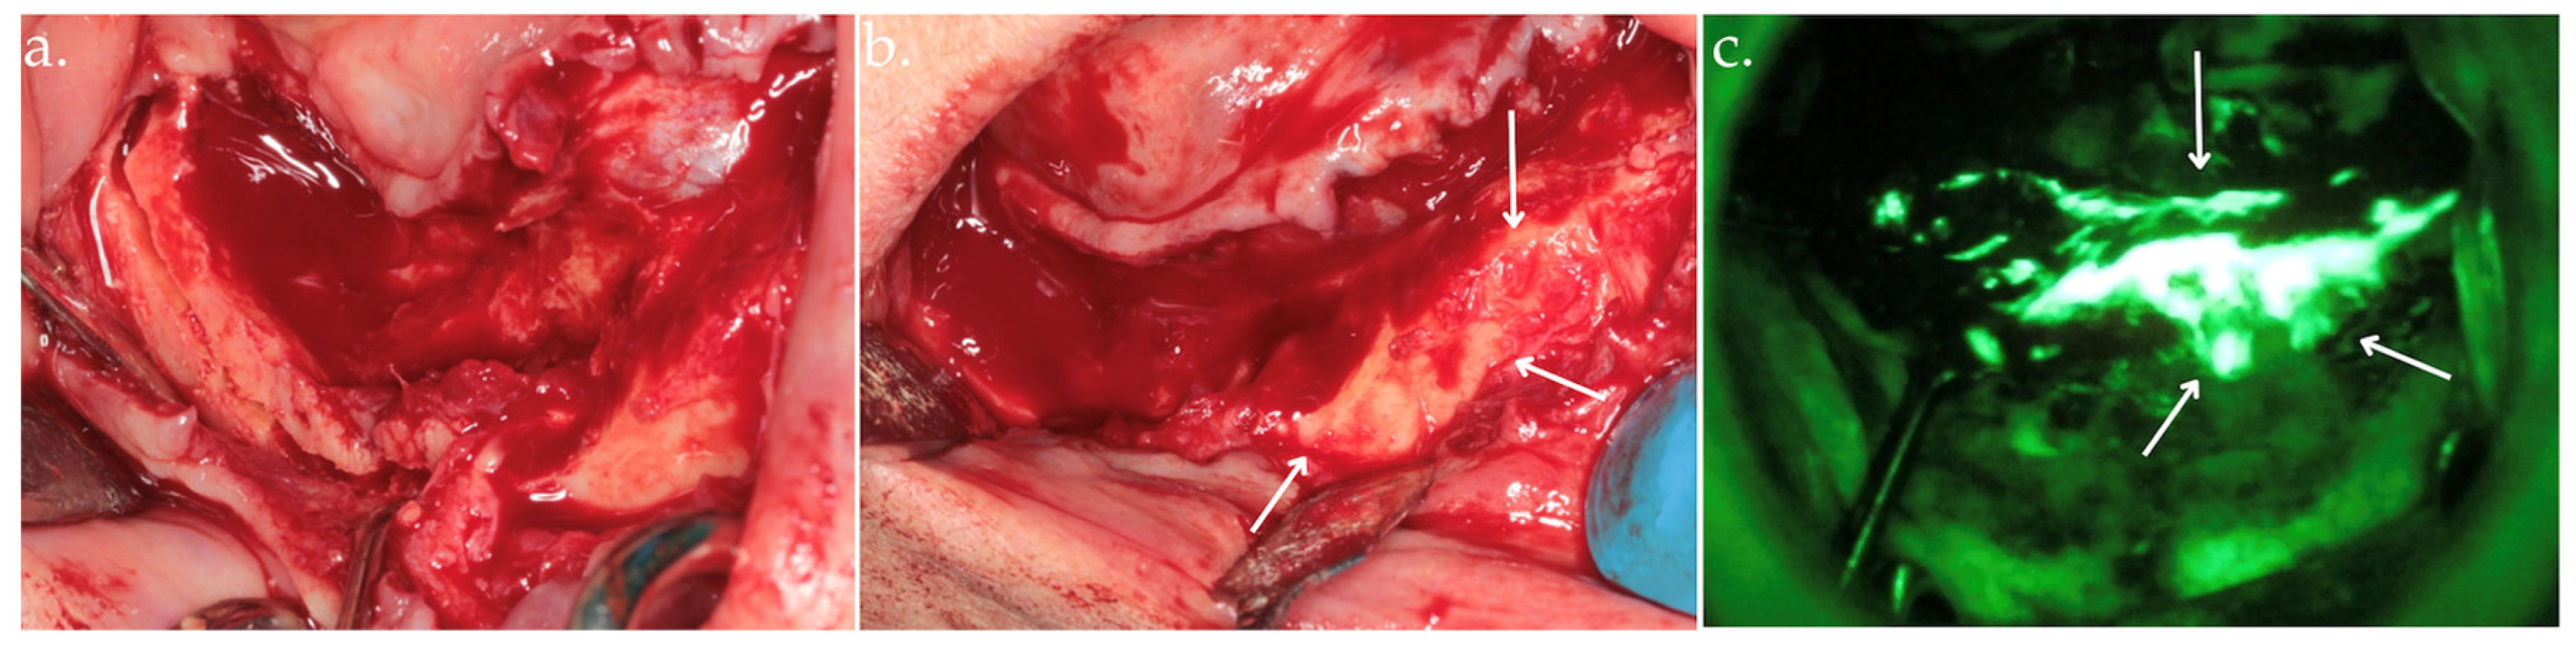

Figure 3.

Delineation of margins and bone block removal in the clinical view (a,b), followed by autofluorescence imaging of the site post-excision (c).

Figure 5.

Osteotomy (a); osteoplasty using Er:YAG laser with arrows indicating viable bone (b), up to the identification of highly hyperfluorescent bone (arrows), confirming the clinical assessment (c).